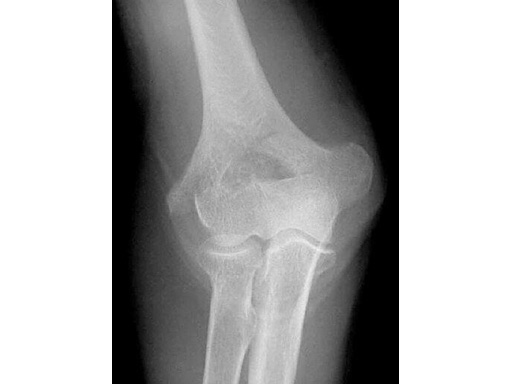

40-year-old man, 13-C3 fracture treated with DHP.